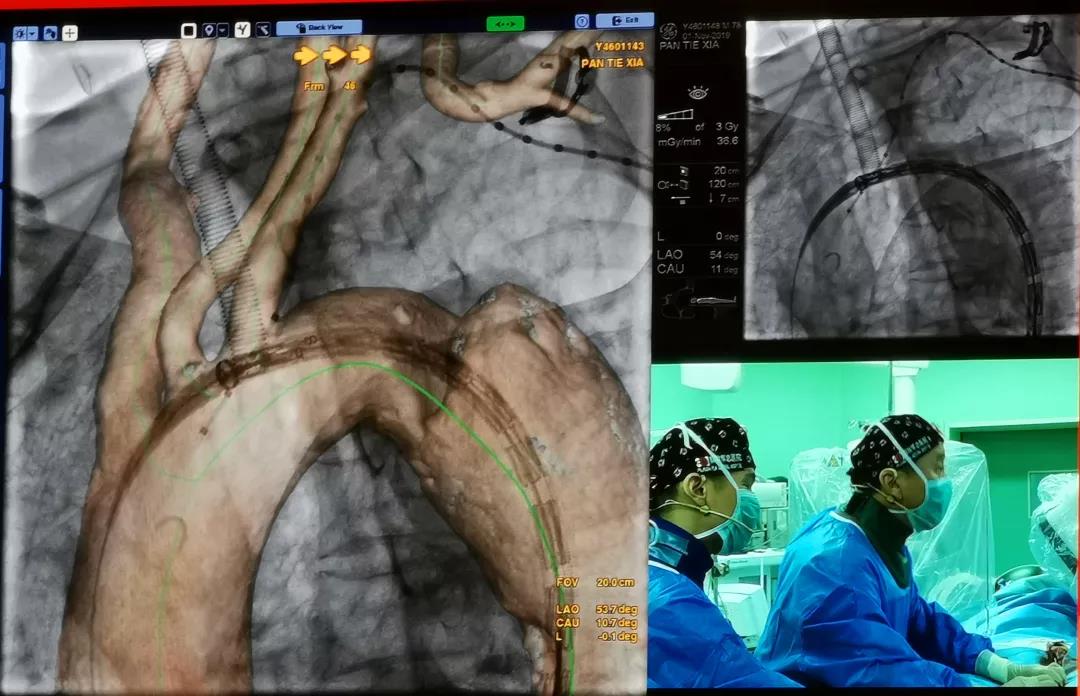

中国人民解放军总医院郭伟教授共演示了3台手术,别离是选取Ankura?支架医治Stanford B型慢性胸自动脉夹层,选取Lifeflow?IBD髂动脉分叉支架系统和Fustar?可调弯鞘在医治腹自动脉瘤时沉建右侧髂内动脉的病例。另表,郭伟教授还演示了一台使用Ankura?支架和新型G-Branch?胸腹自动脉覆膜支架系统沉建内脏动脉全腔内建复胸腹自动脉瘤的病例。郭教授从患者病变情况和医治难点、手术规划、G-Branch?支架产品设计特点及术中操作重点等方面具体介绍了手术过程。手术获得了极大的成功,术后造影显示,瘤体断绝,内脏四分支血管血流畅达,且主体支架与分支支架衔接处无内漏。与会专家对此杰出的病例暗示尤为赞叹,积极与郭伟教授探求G-Branch?支架的创新之处和将来使用方向。郭教授暗示,多分支动脉的腔内沉建是胸腹自动脉瘤微创医治的一个技术高地,也是国际性难题。G-Branch?支架的利用,为胸腹自动脉瘤的患者提供了更为优良的解决规划,等待将来更多的临床利用和循证医学证据将证实其优越性。

中国人民解放军总医院手术直播《Ankura?支架腔内建复胸自动脉夹层》

中国人民解放军总医院手术直播《Lifeflow? IBD支架在腹自动脉瘤的腔内建复术中的利用》

中国人民解放军总医院手术录播《G-Branch?多分支支架医治胸腹自动脉瘤》